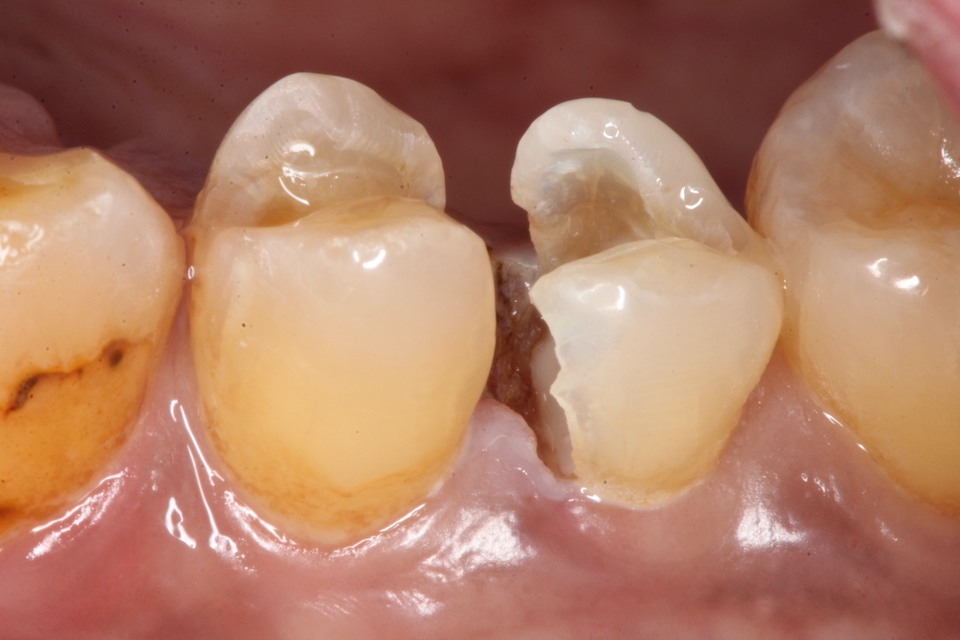

下顎7番の頬側歯茎部カリエスの原因 2025.06.04